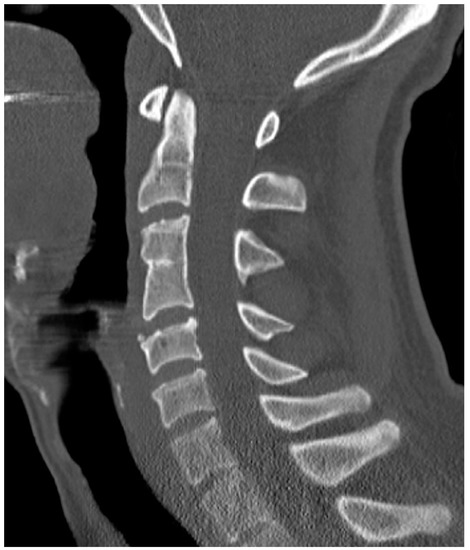

Are Congenital Cervical Block Vertebrae a Risk Factor for Adjacent Segment Disease? A Retrospective Cross-Sectional CT and MR Imaging Study

Adjacent segment disease (ASDI) is a well-described complication of spinal fusion surgery that may ultimately lead to spinal stenosis and repeated surgical intervention. Although congenital block vertebrae also present with degenerative changes in the adjacent segments, this has not yet been systematically investigated. The aim of this study was to assess the presence and degree of ASDI in congenital cervical block vertebrae. Methods: A total of 51 patients with congenital vertebral fusion in one cervical segment were analysed in this IRB-approved retrospective cross-sectional study using available CT/MR imaging. Exclusion criteria were prior spinal surgery and the presence of additional hereditary abnormalities. We assessed the severity of degenerative changes using a sum score. The sum score for adjacent and non-adjacent segments was then divided by the highest possible degeneration score, which resulted in a ratio of severity for adjacent and remaining segments (ranging from 0 to 1). Results: Overall, 35 of 51 patients (68.6%) showed evidence of ASDI, and 34 of 51 patients (66.7%) also showed degenerative changes in the remaining segments. The severity score was significantly higher (p = 0.025) in the segments adjacent to the congenital block vertebrae (mean value 0.307) compared to the non-adjacent segments (mean value 0.188). Conclusions: Our results suggest that ASDI is also caused by congenital block vertebrae of the cervical spine. Full article

Figure 1